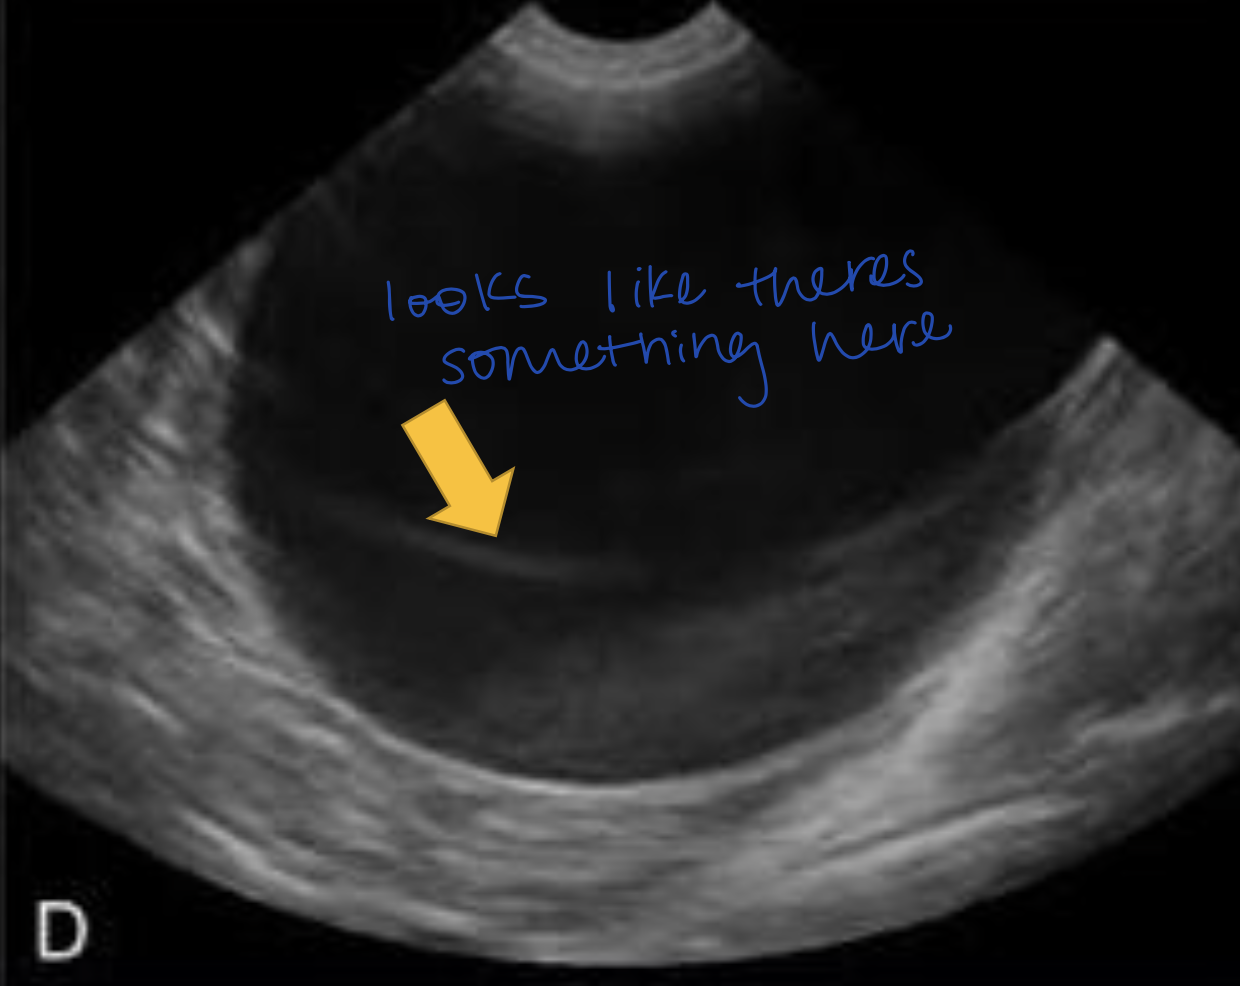

What ultrasound artifact occurs when sound waves bend as they hit a curved surface tangentially?

Edge-Shadowing Artifact

Hypoechoic lines are NOT real